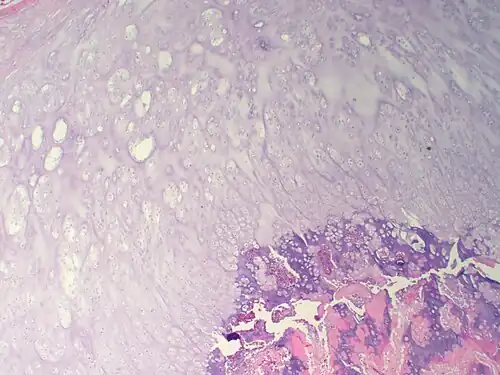

![]() Mikrografia kostniakochrzęstniaka | |